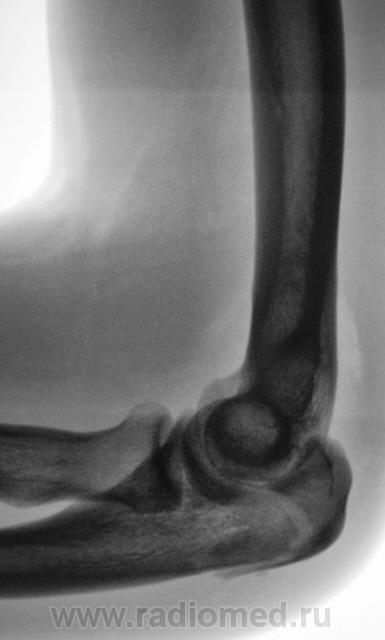

Травма.     Пациент направлен на рентгенографию локтевого сустава.

Перелом локтевого отростка - на операцию

Если рассуждать с точки зрения только диагностики перелома - нет, так как перелом хорошо виден и на стандартных проекциях. С точки зрения дальнейшей лечебной тактики - да. Так как косые проекции выявили безусловную необходимость оперативного лечения.